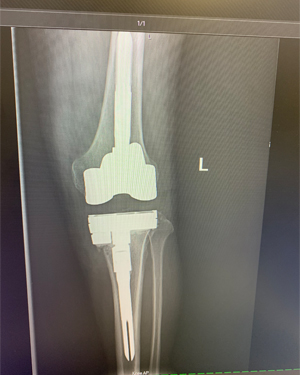

Revision Knee Joint Replacement- Two Weeks after Surgery

Ms. D. Z, is 2 weeks from Right knee replacement and 2 months from Left knee replacement.

This is Ms. D. Z, she is 2 weeks from Right knee replacement and 2 months from Left knee replacement. She is walking well with just a cane at 2 weeks post op.